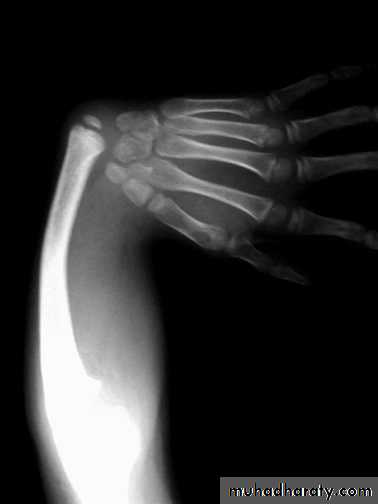

Radial club hand

Absence of whole or part of radiusHand is in radial deviation

Isolated or associated other anomalies (cardiac, blood, vertebral, GI)Rx : manipulation + splintage